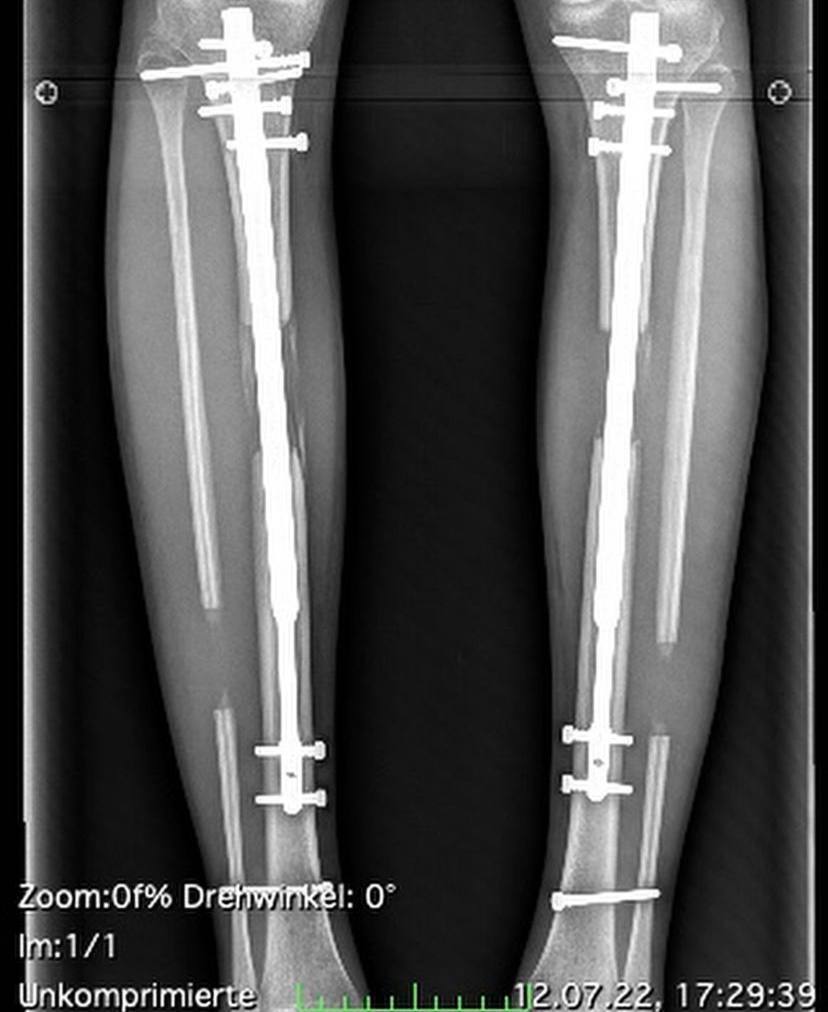

За операцию модель отдала 124 тысячи долларов (4,5 миллиона гривен). На процесс восстановления и лекарства она потратила еще около 36 тысяч долларов (1,3 миллиона гривен). В рамках процедуры, Терезии сломали бедренные кости двух ног, вживили в них телескопические штыри, которые в течение трех месяцев ежедневно вытягивали на миллиметр. Затем девушка перенесла процесс восстановления с болями в нервах, сухожилиях и мышечных тканях.